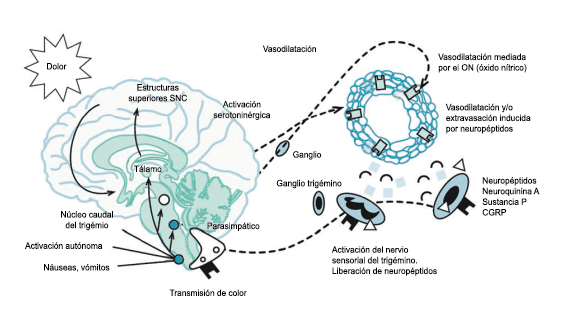

Todo lo mencionado contribuye al fenotipo del migrañoso y son vías que continuamente se están explorando para el desarrollo de nuevas terapias agudas y preventivas del dolor, más seguras y eficaces. Sin embargo, existe una controversia que gira en torno a dos cuestiones: la iniciación y el origen del dolor además de que todavía no se conoce el origen de los mecanismos neuronales que subyacen a la condición primaria en las personas susceptibles. Definitivamente la migraña implica la activación y sensibilización de las vías trigeminovasculares, así como el tronco cerebral y los núcleos diencefálicos(88). La vía aferente comienza en las aferentes vasculares nociceptivas de la duramadre que están para advertir, no para localizar. Su proyección al tálamo y la corteza y como se regula esta vía en cada nivel y por múltiples sistemas, ofrece la posibilidad de comprender los síntomas complejos y orientar las terapias. Los ataques comienzan como síntomas premonitorios, dificultad para concentrarse, bostezos, fluctuaciones del humor; y cambios homeostáticos, como la alimentación y el equilibrio de líquidos, que pueden incluir sensibilidades más generalizadas, como fotofobia y fonofobia. La fase premonitoria da paso a la fase de dolor con el sufrimiento acompañante y termina en una fase posdrómica de sentirse agotado por la experiencia. (Figura 1)

El aura de la migraña, al menos en su sentido clásico, tiene relación con la depresión cortical que se propaga por la corteza cerebral y participa como un actor paralelo cuando se producen las crisis. (Figura 2)

La fisiopatología de la migraña había surgido de una consideración histórica de los “humores” hasta mediados del siglo XX con la ahora desaparecida Teoría Vascular. Pero aún se podría decir que hay tres preguntas: ¿por qué, cómo y cuándo? Por qué: se acepta en gran medida que la migraña es una tendencia heredada del cerebro a perder el control de sus vías de acceso de impulsos. Cómo: la ahora clásica vía aferente nociceptiva vascular de la duramadre del trigémino ofrece una hoja de ruta del ataque. Cuándo: los ataques de migraña surgen debido a un trastorno del procesamiento sensorial del cerebro que probablemente sea cíclico, influenciado por la genética y el medio ambiente.

En la primera fase (figura 3), premonitoria, que precede a la cefalea, los sistemas del tronco encefálico y diencefálico modulan las señales aferentes, la fotofobia a la luz o la fonofobia al sonido, comienzan a disfuncionalizarse y eventualmente a evolucionar a la fase de dolor y con el tiempo a la fase de resolución o posdrómica. Aproximadamente en un tercio de los pacientes con migraña, sus ataques están asociados con déficits neurológicos, que incluyen perturbaciones corticales, denominadas colectivamente aura de migraña(3).

La importancia de la vasculatura intracraneal, o su inervación de fibras nerviosas, sigue siendo significativa. Los estudios de Ray y Wolff(94) demostraron que la estimulación de la duramadre, particularmente alrededor de los vasos sanguíneos durales y cerebrales, puede generar dolor similar al de la cefalea, además de náuseas, mientras que la estimulación lejos de los vasos fue ineficaz. Como se describió anteriormente, los vasos sanguíneos de la duramadre están ricamente inervados por axones nociceptivos no mielinizados (fibras C) y mielinizados (fibras Aδ) que se originan en el ganglio del trigémino y contienen neuropéptidos vasoactivos (serotonina, dopamina, histamina, péptido relacionado con el gel de la calcitonina). Estos datos consolidan la teoría de que la cefalea en la migraña está mediada por la activación de las fibras nerviosas nociceptivas que inervan los vasos sanguíneos meníngeos. La pregunta clave es qué hace que estas fibras se activen durante la migraña. Una propuesta en la década de 1980 fue que una “inflamación neurogénica estéril” de las meninges durales puede resultar en la activación de la inervación perivascular para desencadenar la migraña(95). La activación está impulsada por la liberación dural local de mediadores inflamatorios endógenos como CGRP, sustancia P, neuroquinina A y prostaglandinas, que aumentan el flujo sanguíneo local (predominantemente impulsado por CGRP), la fuga de proteínas plasmáticas de los vasos sanguíneos, la desgranulación de mastocitos y la agregación de las plaquetas.

Un principio importante de esta teoría es que el desencadenante principal de la migraña proviene de la periferia, en los vasos sanguíneos de la duramadre, con la activación del sistema trigeminovascular proveniente del disparo de las neuronas trigeminales periféricas de primer orden en respuesta a una lesión nociceptiva o señales provenientes de las meninges que liberan mediadores neuroinflamatorios. La activación sostenida de las neuronas nociceptivas meníngeas durales provoca la activación secuencial y la sensibilización de las neuronas trigeminovasculares de primer orden (nociceptores periféricos), segundo orden (a nivel del TCC-complejo trigémino cervical) y tercer orden (trigeminotalámico), (Figura 5) así como la activación ascendente del cerebro, tallo y otras estructuras diencefálicas(97).

El dolor de cabeza asociado con un ataque de migraña, puede incluir la región frontal, temporal, parietal, occipital y cervical alta, es consecuencia de la activación del sistema trigeminovascular. (Figura 10)

La anatomía del sistema trigéminovascular ha sido bien descrita durante los últimos 70 años y esto ha ayudado a comprender la fisiopatología de la migraña y la distribución de su dolor. Se sabe que el cerebro es en gran parte insensible, pero un rico plexo de fibras nerviosas nociceptivas que se originan en el ganglio del trigémino inervan los vasos sanguí- neos de la piamadre, la aracnoides y la duramadre, incluidos el seno sagital superior y la arteria meníngea media, así como las grandes arterias cerebrales. (Figura 11) (23)

La inervación nociceptiva de la vasculatura intracraneal y las meninges incluye proyecciones axonales no mielinizadas (fibras C) y mielinizadas delgadas (fibras Aδ), principalmente a través de la división oftálmica (V1) del nervio trigémino, pero también, en menor medida, a través del nervio maxilar. (V2) y divisiones mandibulares (V3). También hay inervación neuronal de la duramadre desde los ganglios de la raíz dorsal cervical (24) (Figura 12).

Los terminales axónicos de las fibras nerviosas nociceptivas que inervan la duramadre contienen neuropéptidos vasoactivos CGRP, sustancia P, neurocinina A y péptido activador de la adenilato ciclasa pituitaria (PACAP)(25) (Figuras 13 y 14), que se cree que son liberados tras la estimulación que causa la vasodilatación de los vasos durales y piales(26) (Figura 15).

Hay una proyección aferente central desde el ganglio del trigémino que ingresa a la médula caudal del tronco encefálico, a través del tracto del trigémino, que termina en el núcleo espinal del trigémino caudalis (TNC), así como la médula espinal cervical superior (C1–C2). (Figura 16)

Las fibras nociceptivas Aδ y C terminan predominantemente en las láminas superficiales, I y IIo, así como en las láminas más profundas V–VI del TNC y extensión cervical. La estimulación de la vasculatura dural en modelos animales, incluidos los senos transverso y sagital superior y la arteria meníngea media, da como resultado la activación de las neuronas en las regiones TNC, C1 y C2 de la médula espinal cervical, conocidas en conjunto como el complejo trigeminocervical (TCC).

Estos datos sugieren que el núcleo del trigémino se extiende hasta el asta dorsal de la región cervical superior en un continuo funcional que incluye la extensión cervical, ello explica la distribución de la percepción del dolor en la migraña sobre las regiones frontal y temporal, además de la participación de parietal, occipital y regiones cervicales superiores(27).

Por lo tanto, se cree que la naturaleza intensa y pulsátil del dolor en la migraña es el resultado de la activación, o la percepción de activación, de estas entradas nociceptivas de las estructuras intracraneales y extracraneales, que convergen y se transmiten a través del TCC. (Figura 17)

Toda la información nociceptiva de las estructuras craneovasculares se transmite a través del TCC y mediante conexiones ascendentes a otras áreas del tronco encefálico y el diencéfalo, involucradas en el procesamiento del dolor y otra información sensorial. La activación de la vía antes mencionada contribuye a la percepción del dolor durante la migraña y también a los síntomas autonómicos, endocrinos, cognitivos y afectivos que duran todo el episodio migrañoso.